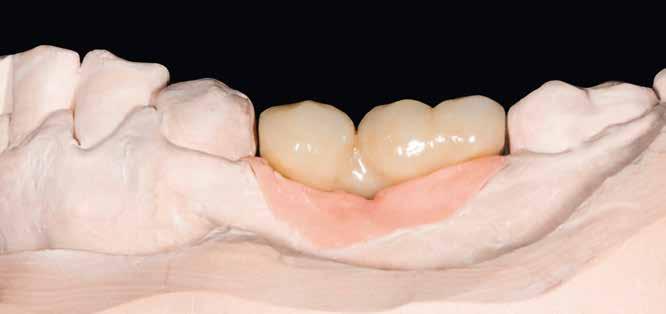

1–2. képek: Kiindulási helyzet.

3. kép: Új teleszkópos fogpótlás az 16, 15, 13, 23 és 27 fogakra.

Teleszkópos munka, élő eset bemutatásával ismertetem, mi az, ami már lehetséges. A munkaasztal-szkenneren kívül bevetésre került a digitális munkafolyamatok során egy intraorális szkenner (IOS) is. A 3D nyomtatású testek gyártása a laboratóriumban LCD- és DLP nyomtatókkal történt. A fémes komponenseket szelektív lézerolvasztásos (SLM) technológiával készíttettük.

Kiindulási helyzet

A páciens látlelete a következő:

• krónikus általános parodontitis

• a 24-től terjedő parodontális fekély

• hatástalan kapcsos felső fogpótlás (1-2. képek)

Terápia

A kezelőorvos (dr. Werner Knapp, Würzburg) ennek alapján a következő terápiát javasolta:

• a 24-es fog extrakciója, illetve az 12 és 22 fogak extrakciója előrehaladott szövetveszteség okán

• szisztematikus parodontitis-terápia

• új, teleszkóp-elhorgonyzású felső fogpótlás az 16, 15, 13, 23 és 27 fogak felhasználásával (3. kép)